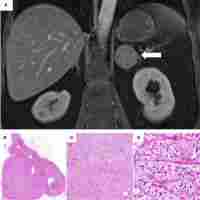

| Abstract | Background Cushing’s disease (CD) is rare in pediatric patients. It is characterized by elevated plasma adrenocorticotropic hormone (ACTH) from pituitary adenomas, with damage to multiple systems and development. In recent years, genetic studies have shed light on the etiology and several mutations have been identified in patients with CD. Case presentation A girl presented at the age of 10 years and 9 months with facial plethora, hirsutism and acne. Her vision and eye movements were impaired. A quick weight gain and slow growth were also observed. Physical examination revealed central obesity, moon face, buffalo hump, supra-clavicular fat pads and bruising. Her plasma ACTH level ranged between 118 and 151 pg/ml, and sella enhanced MRI showed a giant pituitary tumor of 51.8 × 29.3 × 14.0 mm. Transsphenoidal pituitary debulk adenomectomy was performed and immunohistochemical staining confirmed an ACTH-secreting adenoma. Genetic analysis identified a novel germline GPR101 (p.G169R) and a somatic USP8 (p. S719del) mutation. They were hypothesized to impact tumor growth and function, respectively. Conclusions We reported a rare case of pediatric giant pituitary ACTH adenoma and pointed out that unusual concurrent mutations might contribute to its early onset and large volume. |